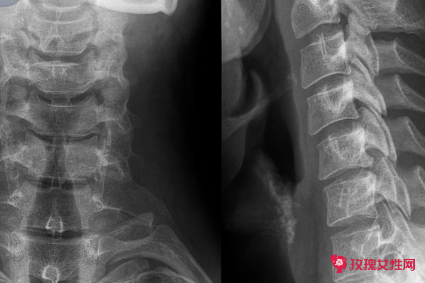

颈椎生理曲度变直的恢复方法

颈椎生理曲度变直后,可以通过牵引治疗、物理治疗、微创治疗等方式,恢复颈椎生理性弯曲。

颈椎生理曲度变直可以通过以下几种方法进行治疗:

第一、颈部制动、颈托外固定、卧床休息,可以减少颈部负重,使颈部肌肉逐渐松弛,促进颈椎生理曲度恢复;

第二、颈椎牵引,每日1-2次,每次30分钟,可以使颈部肌肉解除僵硬、颈椎小关节恢复对合关系,并增宽颈椎间隙,使椎间盘还纳,可以促进颈椎生理曲度恢复;

第三、通过手法按摩,使颈后部、颈侧方及胸锁乳突肌痉挛的结节散开、减轻或消失,恢复颈椎肌肉顺应性,每日1-2次,15日为一疗程;

第四、颈部微波治疗、超短波治疗、远红外线治疗以及中药离子透入治疗等,可以促进颈部肌肉及颈椎管内血液循环,改善局部炎症反应,促进颈椎生理曲度恢复。